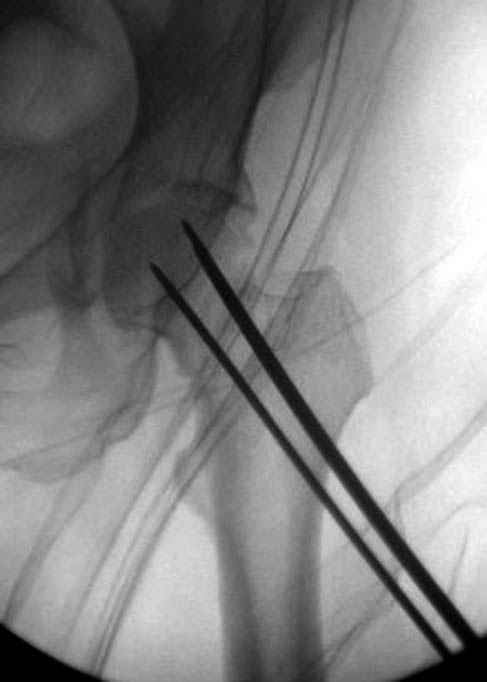

Долгое ожидание повышает риск АВН головки,

рекомендуется ургентная фиксация шейки в первые сутки, а в дальнейшем таз.

В данный момент скелетное вытяжение поучается через перелом шейки, а фиксированный перелом шейки будет участвовать в процессе вытяжения через каннюлированные шурупы.

Перелом шейки смогли зафиксировать через пару дней, ацетабулум до сих пор не оперирован, на вытяжении.